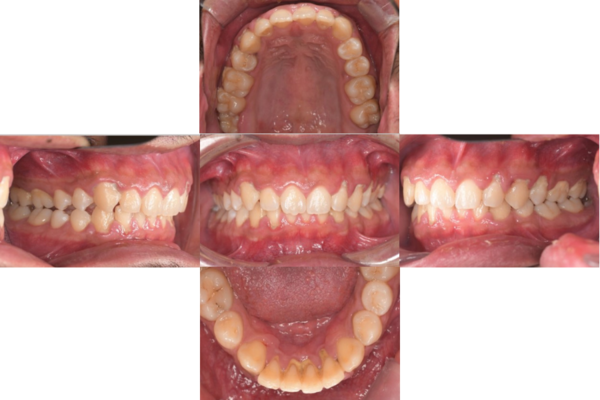

治療内容 1.歯周ポケット検査、資料取り(レントゲン写真14枚・口腔内写真)、歯磨き指導

2.歯磨き指導チェック、縁上の歯石除去

3.縁下の歯石除去4回

4.再評価(歯周ポケット検査・レントゲン写真14枚・口腔内写真)

5.メインテナンス

担当者所見 全体的に出血が見られたのと、奥の歯ぐきは炎症があり歯周ポケットが深かった為、まずは歯ブラシの当て方+歯間ブラシ3Sサイズを使用して頂き炎症を落ち着かせました。

両方毎日使用して頂いた為、スムーズに歯周病治療を行うことができました。毎日のホームケアが不十分だと、なかなか結果に繋がらず、治療期間も長くかかってしまう為、患者様の協力が歯周病治療を成功させるためにはかなり重要になっていきます。

そして一度病気になった歯ぐきは再発しやすい為、今後は3ヶ月に1度の定期的なメインテナンスで、この状態を維持できるよう一緒に管理していきます。